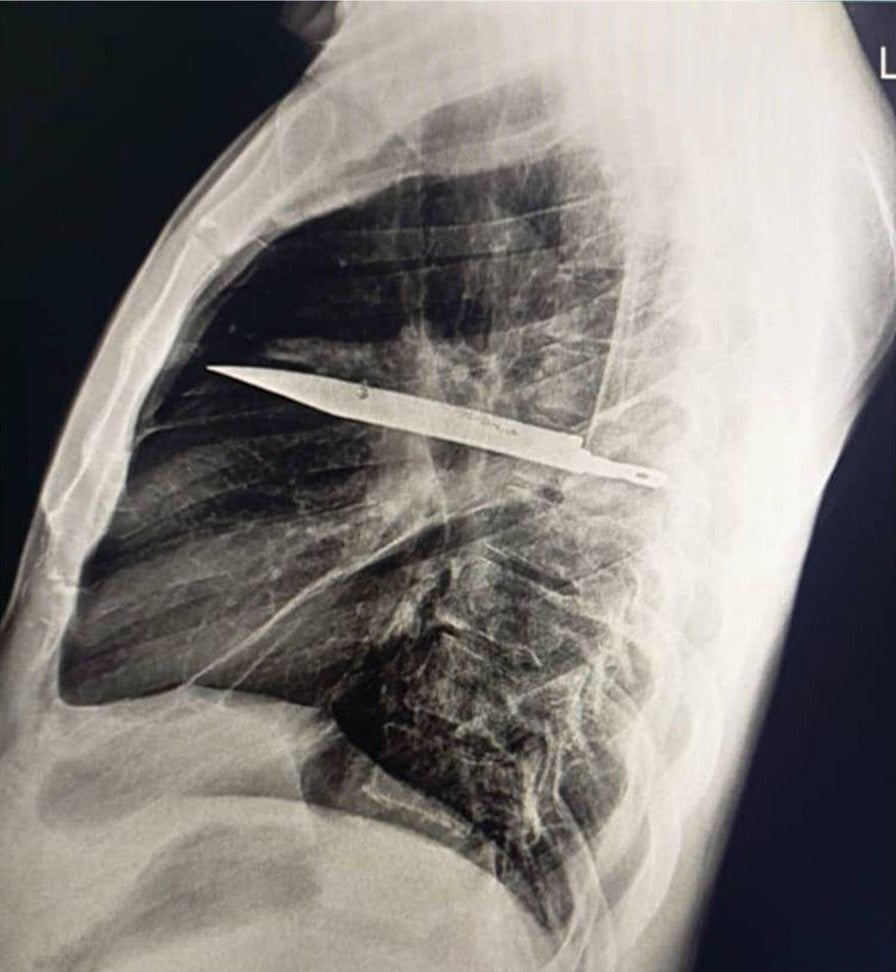

8年間、胸にナイフが刺さったままの男性がいたことが外科症例報告ジャーナルに報告されました。

報告によると、ナイフが刺さったままになっていたのは、44歳のタンザニア人。10日間、乳首のすぐ下から膿がでていたために、病院を訪れました。

男性は、8年前に激しい喧嘩に巻き込まれ、顔、背中、胸、腹部に複数の切り傷を負ったとのこと。

男性は事件後に医療施設で応急処置を受け、創傷は縫合されましたが、止血されたため、レントゲン検査等は行われませんでした。

というのも、検査を行う設備がなかったためです。

男性はその後、今回の症例に至るまで順調な経過を辿りました。

今回、レントゲン検査で胸部にナイフが残っているのが確認されたため直ちに手術が行われ、ナイフを抜去。男性は10日間後に退院しました。

報告は、「残存したナイフが致命的な状況につながる重大なリスクがあった」と述べています。

【閲覧注意】胸にナイフが刺さった状態のレントゲン写真